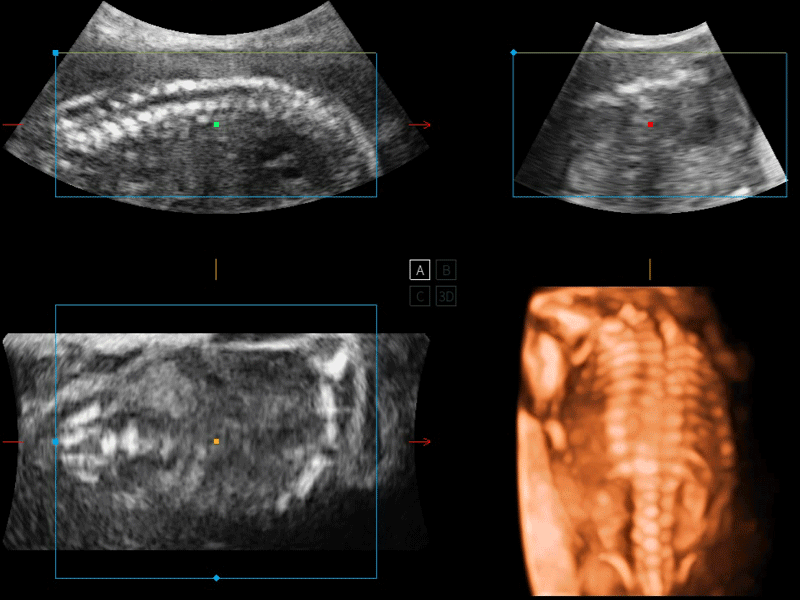

開立醫(yī)療通過不斷的技術(shù)創(chuàng)新,為大眾的生命健康提供持續(xù)關(guān)愛。P12 Plus采用全新一代超聲成像平臺,新平臺旨在將真實(shí)還原組織解剖結(jié)構(gòu)作為首要目標(biāo)。平臺采用全新集成化硬件模塊,搭載新一代芯片,系統(tǒng)性能得到大幅提升,為您的診斷提供了豐富的臨床信息。優(yōu)異的圖像表現(xiàn),豐富的探頭配置,全面的應(yīng)用功能,為您日常診斷提供了可靠的助手。